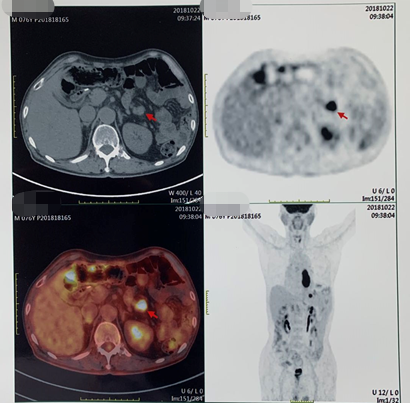

PET/CT(2018-10-22):食管中下段管壁增厚FDG代谢增高,吻合口下方肠壁FDG代谢增高灶;左上腹系膜区多发FDG代谢增高灶,考虑多发转移;后腹膜区及右侧髂血管旁多发小淋巴结FDG代谢轻度增高,倾向转移淋巴结。